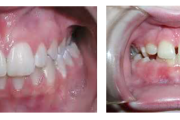

Ülemise hambakaare kitsenemine ehk tagumiste hammaste risthambumus

Hammustades on näha, et alumine hambakaar on laiem kui ülemine. Tagumine risthambumus võib olla kas mõlemapoolne või ühepoolne ja sageli hambakaarte keskjooned hammustades ei ühti. Tagumist risthambumust võib esineda 10 % lastest. Ülemise hambakaare kitsenemine võib olla tingitud Loe edasi »